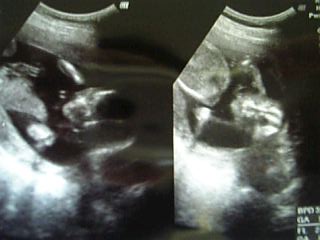

1ヶ月ぶりの検診。

今日はオットも一緒にお腹のベビーの様子を見に行きマシタ。

この日オットは、超音波でウゴウゴウニウニ動く姿とちゃんと週数どおりに育っている吾が子を確認できたとき、感無量で泣きそうになったそうだw。

5ヶ月ということで、そろそろ性別がわかる検診。

ベビーは何度もおマタを見せてくれたけど、イマイチわからない・・・。

左→頭。右脳と左脳がくっきりわかれてマス。

右→おマタ&大腿骨

先月は頭が週数よりも小さめだったけど、今月は4日ほどちょと大きめ。

大腿骨は週数よりも2日ほど小さめ。

まあ、明らかに測り方だと思うので大きさはほぼ週数どおりですな。

とにかくよく動くので、なかなかよい写真は撮れません。